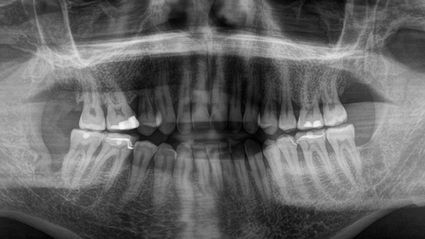

Im Januar 2019, vor sechs Monaten, hatte ich meine Kavitationsoperation in der Swiss Biohealth Clinic. Ich hatte Kavitationen an allen vier Weisheitszahnstellen. Die beiden linken Weisheitszähne waren 2008 raus. Die rechten waren noch da und mussten gezogen werden, um die Karies zu beseitigen.